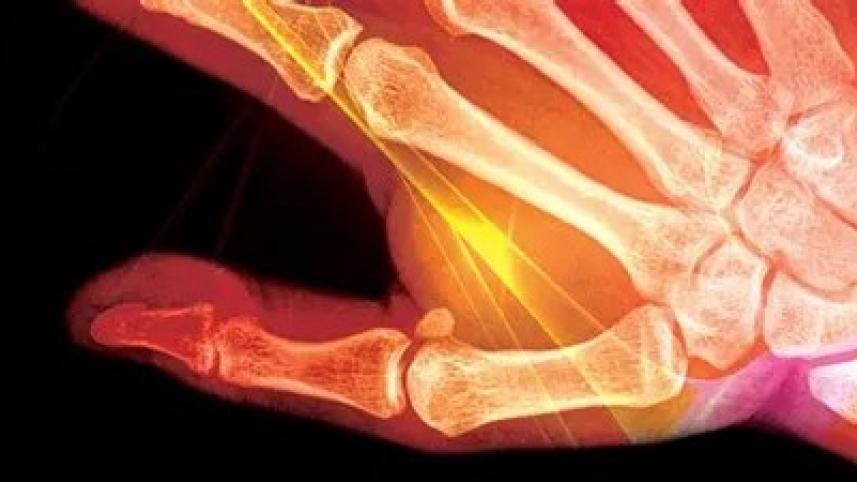

Few specific arthritic ailments often impact both men and women in our country, irrespective of age. Rheumatoid arthritis is often found in women — the patients experience pain in both small and large joints, which includes hands and feet.

Ankylosing spondylitis is a condition that affects the vertebral column. In long-standing cases, it prevents patients from standing straight as a result of developing a stooped-over posture. This is associated with lower back pain. Some arthritic conditions are often associated with skin conditions such as psoriasis leading to psoriatic arthritis.

Although gout is not common in people, if it does occur, treatment should consist of a strict diet without foods that can increase the level of uric acid in the body. Osteoarthritis stems from the knees and mostly impacts the elderly. Although women are mostly affected by this, men too suffer from this condition and so do people who are lean or obese.